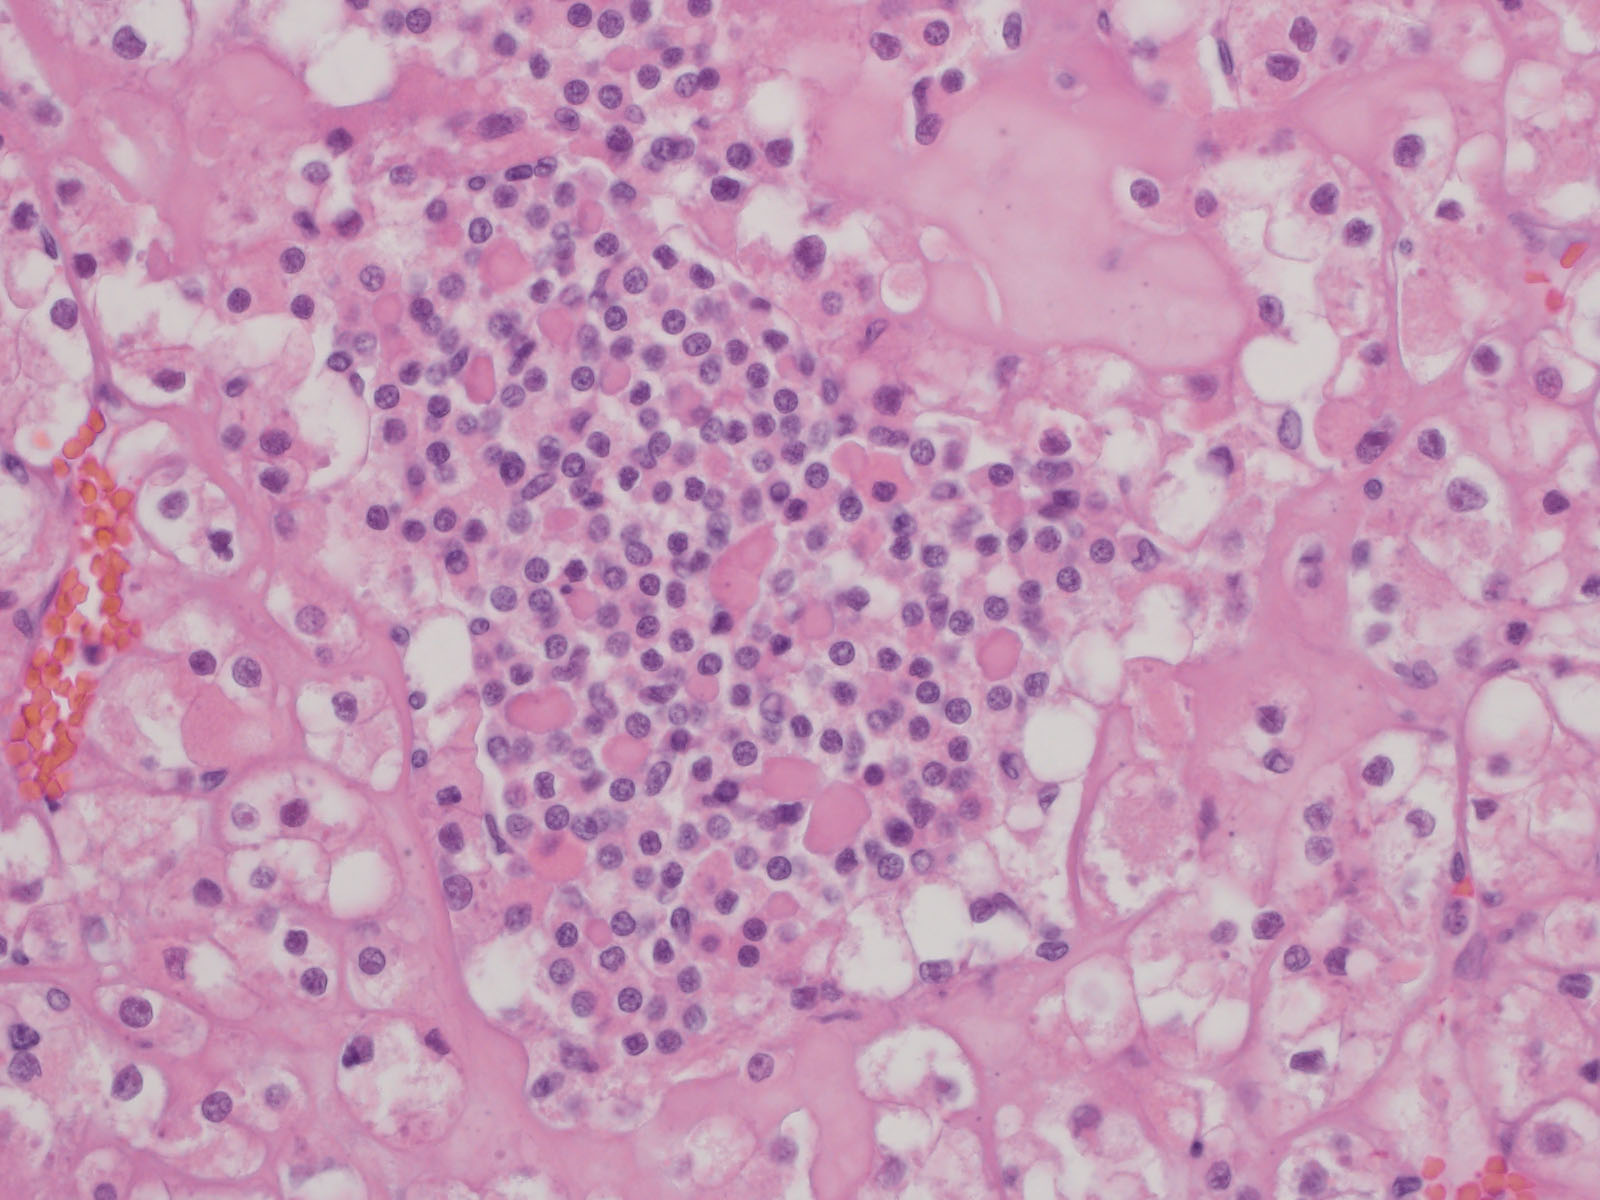

Classification of renal tumors

Case ID: 787